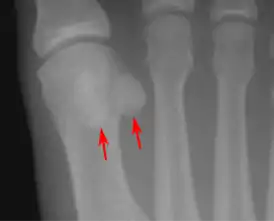

- стопа — две сесамовидные кости в области соединения первой плюсневой кости с первым пальцем (внутри сухожилия короткого сгибателя большого пальца стопы)[3].

Распространённое заболевание стопы у танцоров — сесамоидит. Встречаются также раздвоенные сесамовидные кости, которые могут иметь как врождённый, так и посттравматический характер.